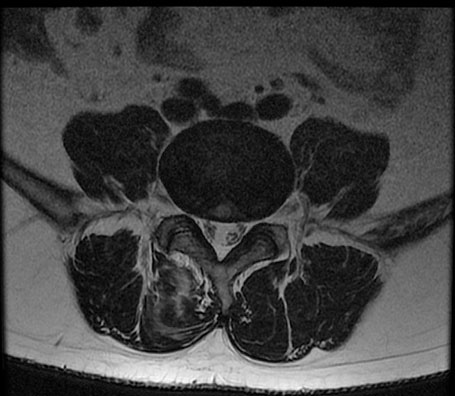

※ After 사진은 6개월 후 촬영된 모습으로, 파열된 디스크가 깨끗하게 흡수된 것을 확인할 수 있습니다.

허리디스크는 비수술 치료를 잘 받으면 튀어나온 수핵이 깨끗하게 흡수되어 없어지는 경향이 있습니다. 특히 파열이 심할수록, 디스크가 찢어져 수핵이 많이 튀어나올수록 오히려 더 잘 흡수되는 경향이 있습니다. 정확히 말하자면, 찢어진 디스크 안으로 재흡수되는 것이 아니라 우리 몸이 튀어나온 디스크를 이물질로 인식해 녹여서 몸속으로 흡수되어 없어지는 것입니다.